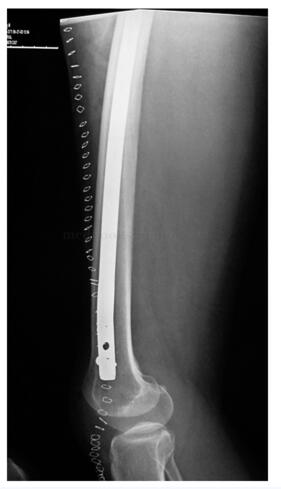

完善术前检查后行右大腿前侧间室肿瘤切除,股骨髓内针固定术。联合麻醉满意后,平卧位。采用大腿前侧梭形切口,自右髂前上棘至右髌骨下方,切除原4条手术瘢痕,自深筋膜浅层向两侧分离,分离至内外侧肌间隔。内侧分离保护股动静脉,分离结扎股神经。自内外侧肌间隔下方向股骨方向分离,至股骨表面。远端在髌骨下方切断髌腱,近端切断股四头肌的起点,其深方在股骨上的止点连同骨膜一同切除(图49‐5)。为防止因大范围切除骨膜造成股骨干病理性骨折,于股骨髁逆行置入带锁髓内针,并锁定远端锁钉(图49‐6)。充分止血,置入伤口负压引流管3 根。分层缝合伤口,术毕。

图49‐6 为预防骨折,带锁髓内针固定后

:患者术后3周开始扶双拐下地运动,并进行大腿局部放疗1月。术后半年,患者轻微外伤后出现右股骨干中段横断骨折,因有预防性内固定存在,骨折无移位(图49‐8),术后1年骨折愈合(图49‐9)。目前患者术后5年,肿瘤无局部复发,无淋巴结转移,无远隔转移(图49‐10)。患者平卧位主动屈髋、屈膝无力,被动屈膝45°,屈髋45°,日常不佩戴支具扶单拐行走,也可以不扶拐行走,轻度跛行。患者自觉功能满意。

图49‐9 术后1年骨折愈合